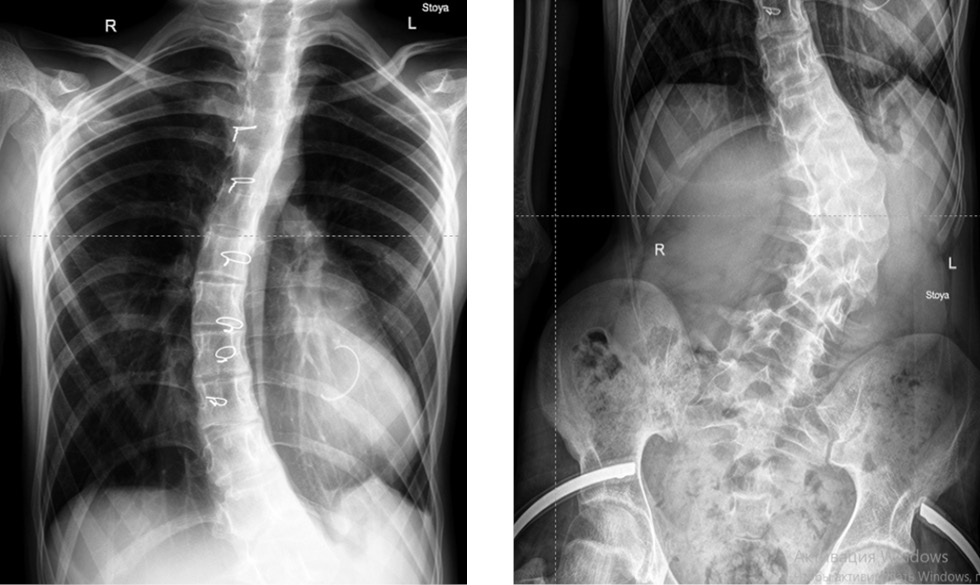

Рентгенография грудной клетки: не выявлено особенностей по сравнению с данными компьютерной томографии, определена деформация позвоночника с основной левосторонней поясничной дугой с вершиной на II позвонке до 78° и грудным правосторонним противоискривлением до 34° в положении стоя (рис. 1).

Рис. 1. Рентгенография позвоночника пациента на протяжении в прямой проекции, в положении стоя: поясничный левосторонний сколиоз с протяженным грудным противоискривлением; серкляжный проволочный шов грудины после продольной стернотомии, опорное полукольцо митрального клапана.